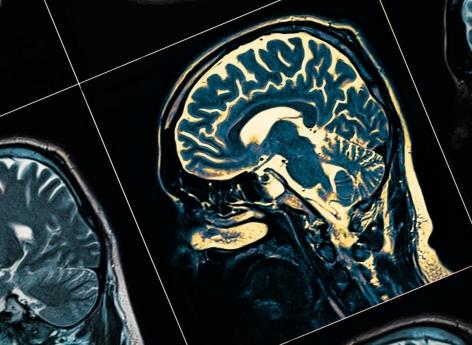

- Les scientifiques ont utilisé des rayons X puissants et des optiques en haute résolution pour réaliser des images en 3D d’échantillons de tissus cérébraux.

Des rayons X pour faire des images 3D

Les scientifiques ont utilisé des rayons X puissants et des optiques en haute résolution pour réaliser des images en 3D d’échantillons de tissus cérébraux. Ceux-ci provenaient de cerveaux sains et de patients schizophrènes. Les clichés obtenus ont démontré plusieurs résultats. Tout d’abord, les structures des neurones sont différentes et uniques chez chaque patient atteint de schizophrénie. Ce premier résultat suggère que la maladie est donc associée à des différences neurologiques structurelles. La seconde observation est que les images de neurones sains étaient relativement similaires, alors que ceux des patients schizophrènes étaient de structures variables, à la fois par rapport aux cerveaux sains et entre eux.